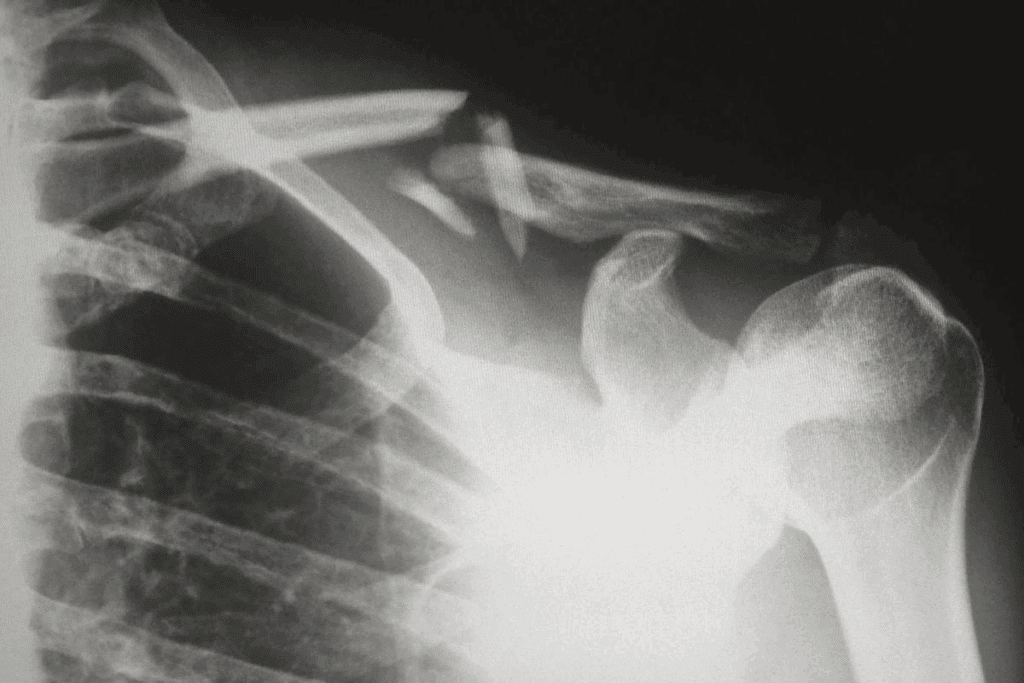

Vascular Complications in Fracture Healing

Good blood flow is key for bone healing. Without it, fractures can heal slowly or not at all.

Poor Blood Supply to Fracture Sites

A fracture site needs blood to heal. Damage to blood vessels or diseases can stop this flow.

Factors Contributing to Poor Blood Supply:

- Trauma to surrounding tissues

- Pre-existing vascular conditions

- Diabetes

- Smoking

Peripheral Vascular Disease Effects

Peripheral vascular disease (PVD) harms blood flow to the limbs. This can slow down bone healing.

| Condition | Effect on Fracture Healing |

| Peripheral Vascular Disease | Reduced blood flow to fracture site |

| Poor Blood Supply | Delayed healing, possible nonunion |

| Compartment Syndrome | Increased pressure, possible tissue damage |

Compartment Syndrome Risks

Compartment syndrome is a serious issue after a fracture. It happens when muscle compartments get too tight, harming blood flow.

Avascular Necrosis Development

Avascular necrosis is when bone tissue dies because of no blood flow. This can happen after a fracture, if the bone’s blood supply is cut off.